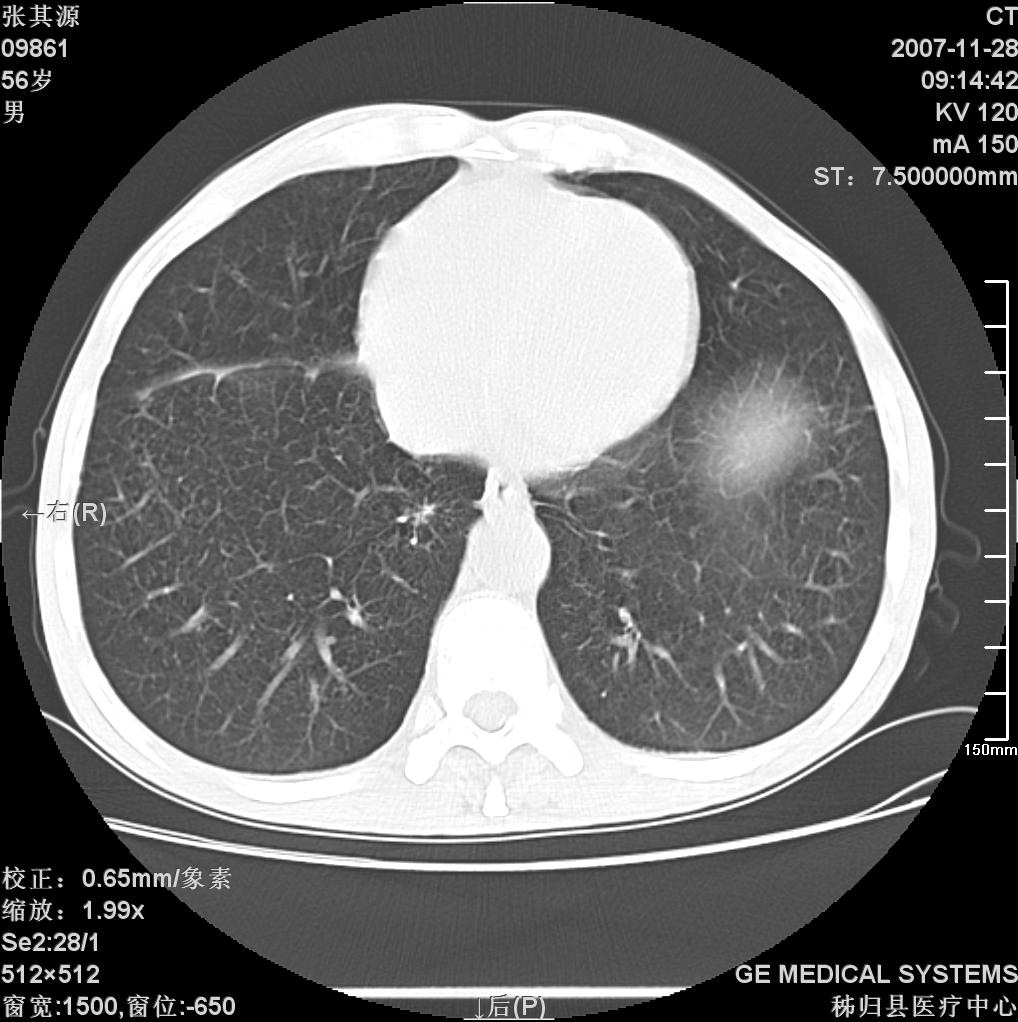

患者因阻塞性黄疸入院,发病前10天持续中等程度发烧.术前检查发现两肺弥漫性病变,请各位大虾会诊,除了考虑急性血源性肺结核外,还有其他什么疾病可能.

补充一下,该患者没有与尘肺相关职业史。请大家帮忙会诊一下,外科医生打算为其做胆总管肿瘤做手术的,现在在等我们的结果。谢谢各位了。

影像符合粟粒型肺tb改变。

考虑tb不排除转移,(隆突处有肿大淋巴结,不好说是结核还是转移引起的)

两肺另见略大结节,结合病史,应考虑转移,有腹部片吗?肺内表现可有:结核?甲状腺癌肺转移?肺泡癌?

双肺多发粟粒样病灶,右肺胸膜下结节样病灶,气管前腔静脉后及隆突下均见肿大淋巴结,结合胆道肿瘤病史首先考虑转移。另外心影密度略低,时间格显示,是否有贫血?查明白再手术吧!